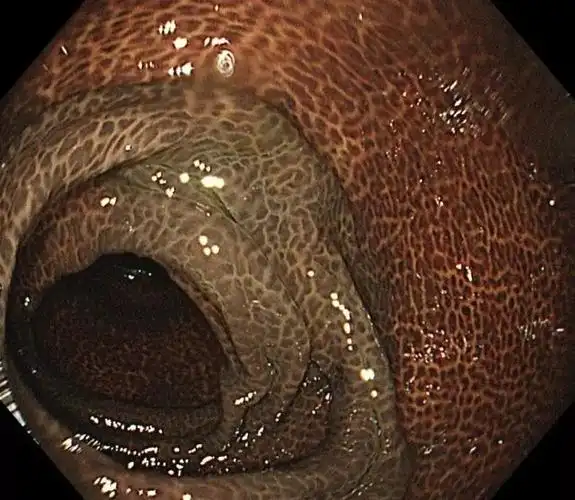

结肠黑变病